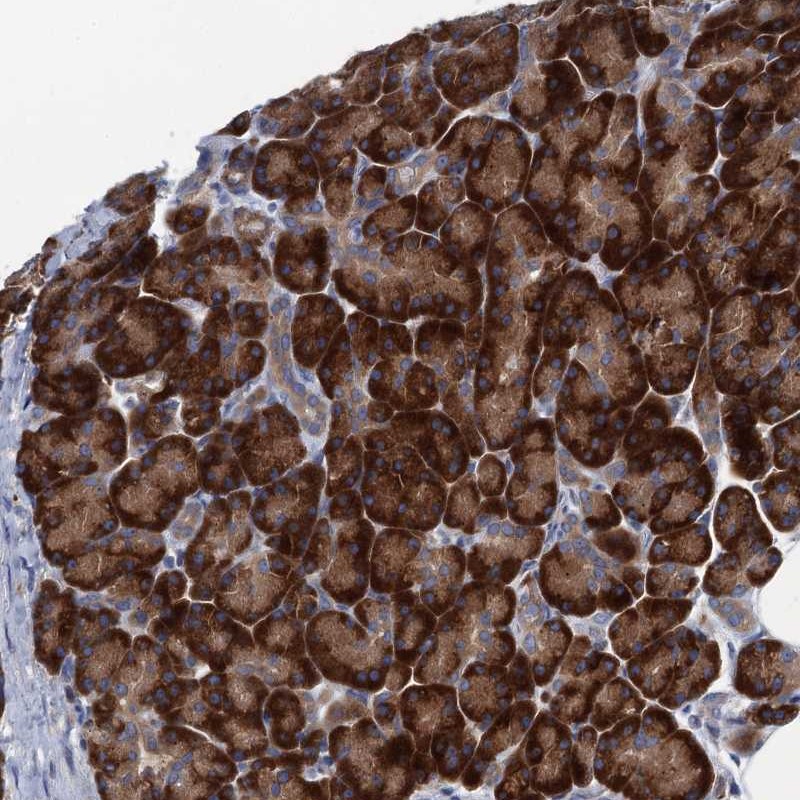

Immunohistochemical staining of human pancreas shows strong cytoplasmic positivity in exocrine glandular cells.